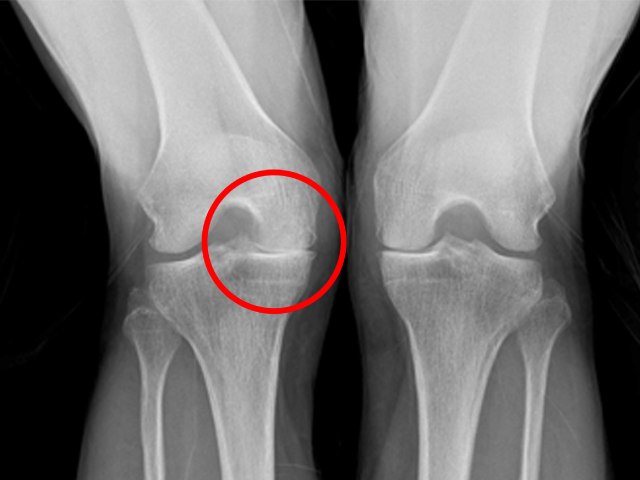

무릎인공관절 전체치환술

수술

치료

ㆍ환자 동의를 받은 자료이며, 이미지 사진은 실물과 다를 수 있습니다.

ㆍ전 : 2020.07.27 / 후 : 2020.08.13 엑스레이 전,후 사진입니다.